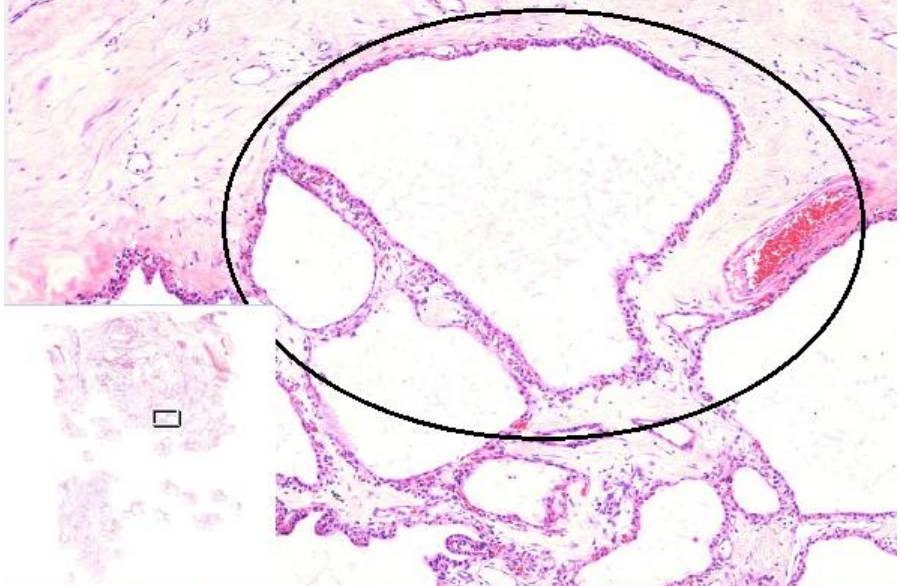

2. Neoplasia cística serosa (A541)

1. Epitélio simples sem mucina

1. Células com núcleo basófilo e pequeno